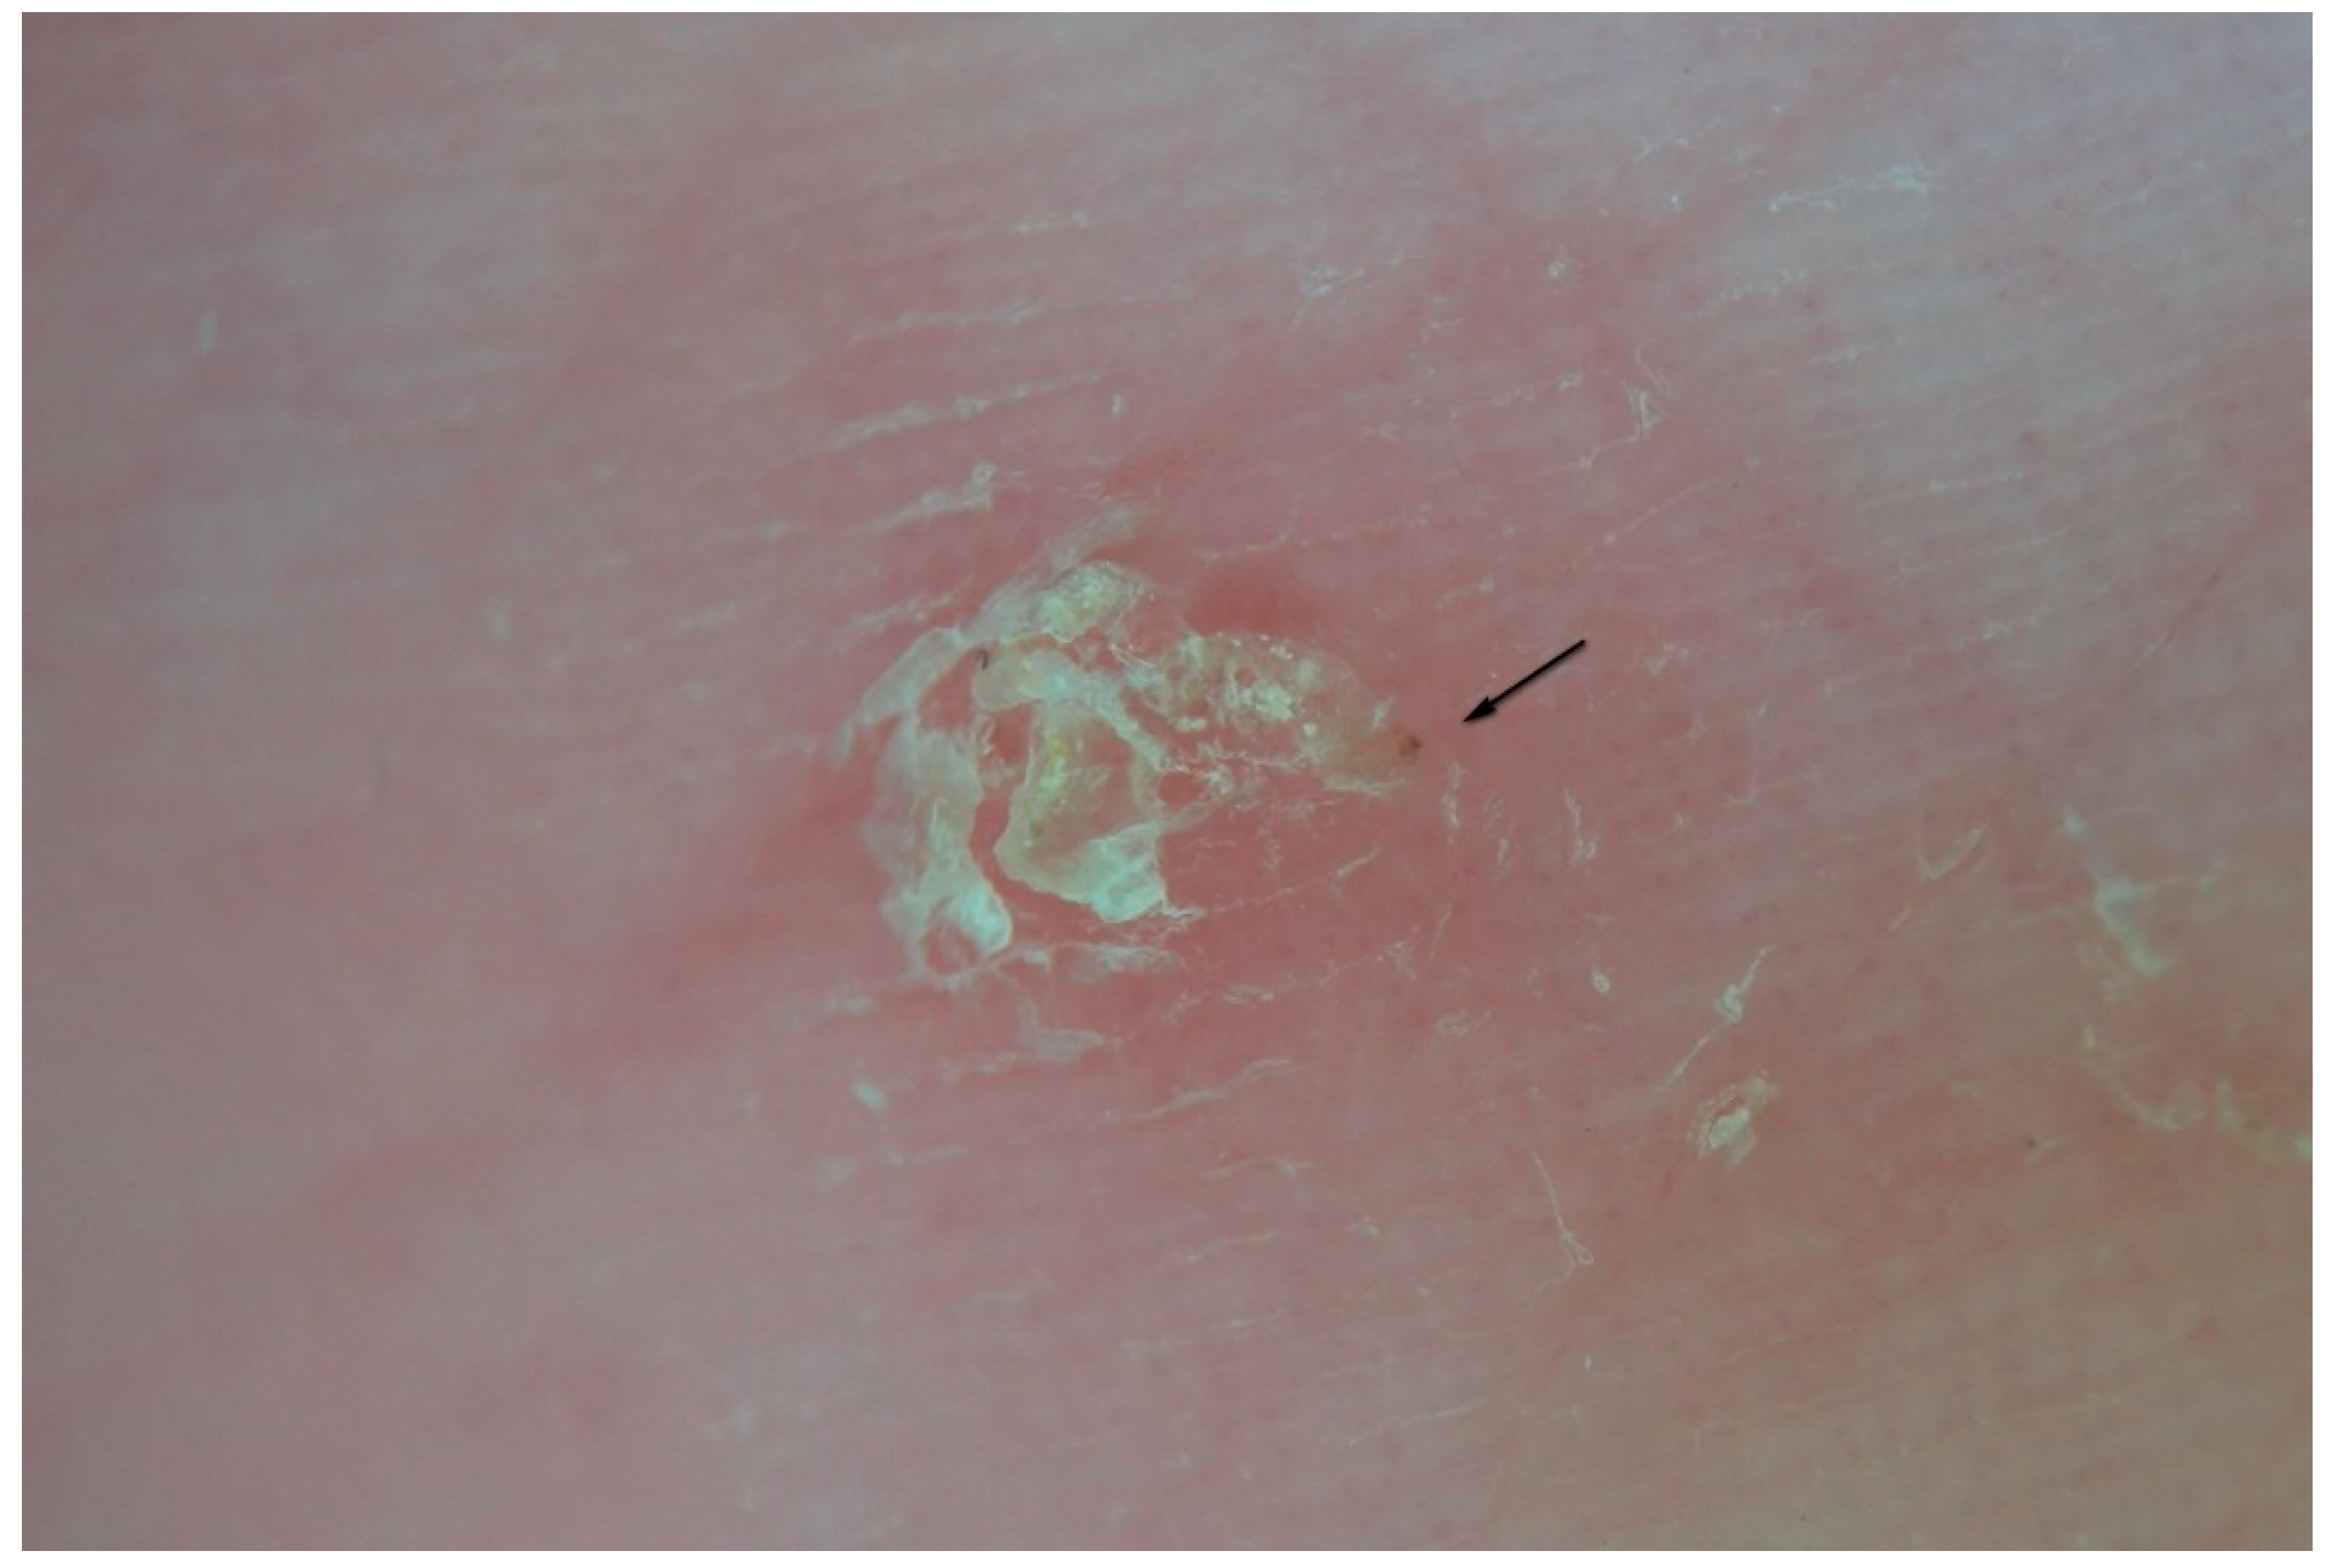

Figure 9.

Inflammatory response to an MGU observed under polarized light dry dermatoscopy of a hand lesion. Next to the mite (black arrows, L-R) the skin is normal, while in the central part of the gallery an erythematous halo (red arrow, L) is evident. Immediately behind the mite, inflammation can also occur in microvesicles trapped in the epidermis (red arrow, R). The tail of the gallery is characterized by keratin collarettes.